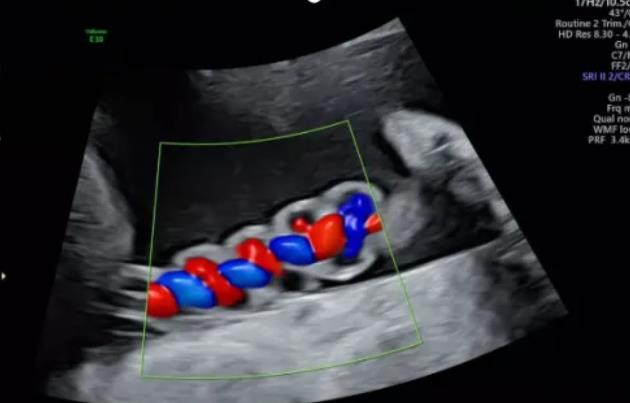

2、臍帶螺旋過松

聲像圖特征:胎兒臍帶縱切面示血管呈平行排列,螺旋稀少,彩色多普勒血流成像示臍帶血管內(nèi)充滿的紅藍(lán)血流呈平行排列,麻花狀螺旋消失。